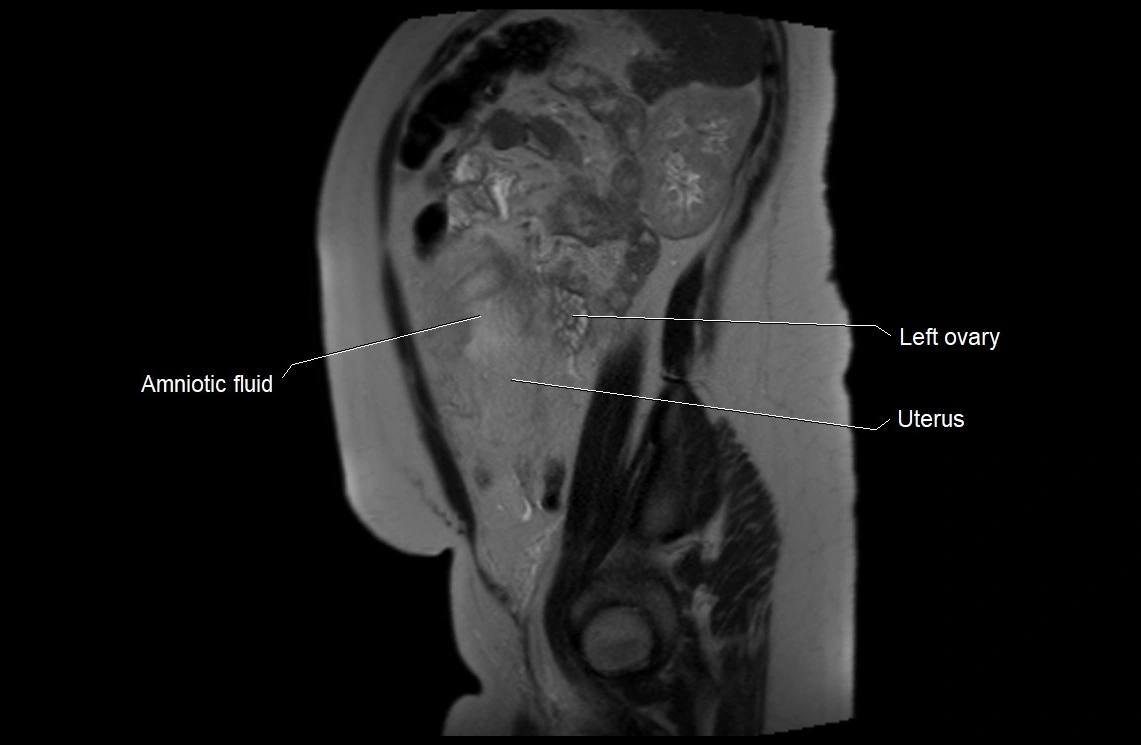

MRI Appearance

T2 HASTE (T2 GRE):

• Amniotic fluid shows very bright hyperintense signal

• Provides natural contrast against fetus and placenta

• Small particles (vernix) may appear as scattered hypointense foci within bright fluid

T1 GRE:

• Amniotic fluid shows low signal intensity (dark)

• Hemorrhage, infection, or proteinaceous content may cause focal or diffuse high signal intensity

MRI image

image